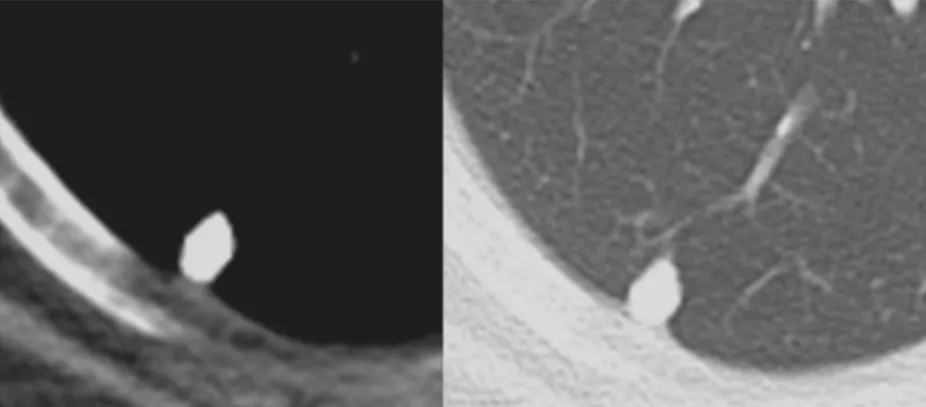

肺裂结节

现在的研究总会提到肺裂结节(PFN)。叶间裂的里边出现一个结节,三角形、多边形、卵圆形或扁豆形,位于胸膜15mm以内范围,典型和不典型PFN主要为良性,主要考虑为肺内淋巴结。